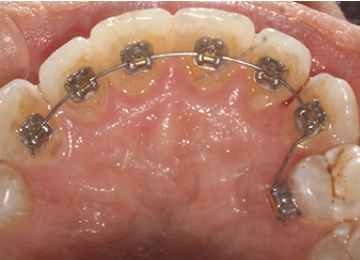

Брекеты Incognito: фото До и После

Крепление брекетов осуществляется за счет специальных замков, предназначенных для каждой единицы. Пазы для замков – вертикальные, благодаря чему деротация зубов проводится без применения эластической цепочки.

Устройство и принцип работы

Аномалии зубного ряда корректируются с соблюдением особенностей.

- Установка замков на внутренней стороне с большой площадью покрытия внутренней стороны.

- С внутренней стороны зубов устанавливаются замки из специального сплава с добавлением золота. Отличительная черта лингвальных брекетов Incognito – обширное покрытие внутренней поверхности зуба тонкой пластиной.

- Для крепления замков предусмотрена специальная дужка, изогнутая по слепкам. Она надежно закрепляет зубы, стягивая их в нужном направлении.

Для толщины брекетов «Инкогнито» не требуется композитная подушка – ее роль играют зубы. При изготовлении брекет-систем используется специальный робот, изгибающий дуги по конкретному рисунку зубной челюсти.